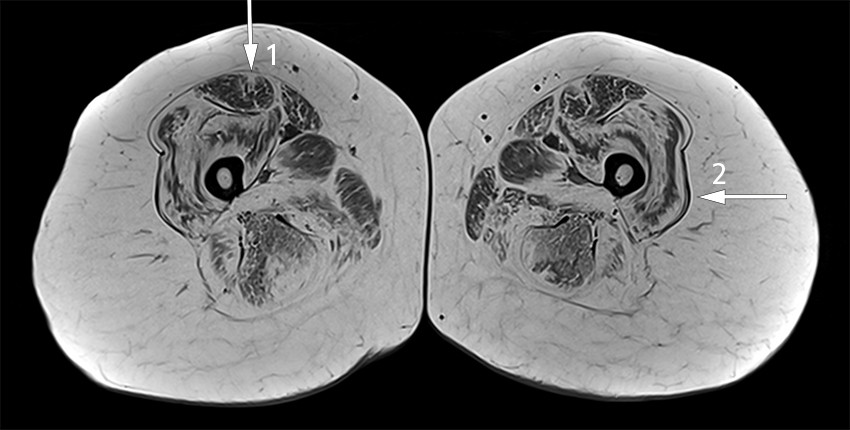

Based on a clinical examination consistent with myopathy, positive genetic testing and previously demonstrated fatty infiltration on MRI, there was no indication for electromyography. With the woman's consent, her clinical presentation was discussed anonymously in a national video conference with colleagues across Norway working with rare muscular diseases. It was recommended that MRI scanning of all muscles be performed, which revealed a characteristic pattern of fatty infiltration, predominantly in the proximal muscles of the upper and lower extremities (Figure 1).

Typical features of Bethlem myopathy are moderate weakness and atrophy of muscles in the trunk and extremities. This tends to be most prominent in proximal and extensor muscles. Slow progression is common, and more than two-thirds of patients aged over 50 years need mobility aids, for example crutches or wheelchairs outdoors (10).

MRI scanning is being increasingly used to investigate diseases affecting the muscles, primarily to select a suitable biopsy site, but also as a diagnostic tool to identify the extent and pattern of muscle oedema and fatty infiltration. Collagen VI-related myopathies such as Bethlem myopathy have a distinct, but not pathognomonic pattern with central fatty infiltration in the rectus femoris muscle and peripheral fatty infiltration in the vastus lateralis muscle with relative sparing of the central region, resulting in a 'sandwich sign' (12–14).